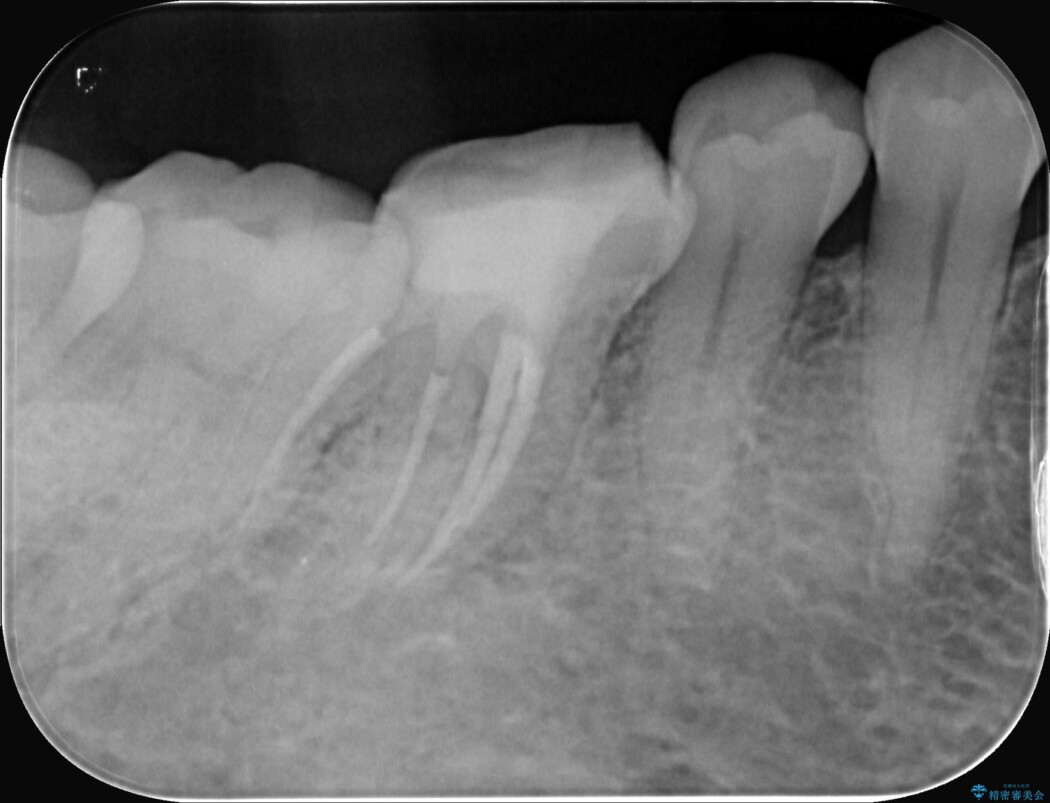

精密検査の結果、根の先に大きな病変が認められますが、根管内が狭窄し湾曲しているため、非常に難易度の高いケースです。

通常の治療器具では奥まで届かず、そのままでは再発や抜歯になるリスクが高いため、マイクロスコープを使用して根の奥まで精密に清掃・殺菌し、歯を残すための治療計画を立てました。

術後の経過は非常に良く、あんなに大きかった膿の袋は消え、健康な骨が再生しているのが確認できました。痛みや腫れも消えて抜歯を免れ、現在は被せ物を入れてしっかりお食事を楽しんでいただけるようになっています。